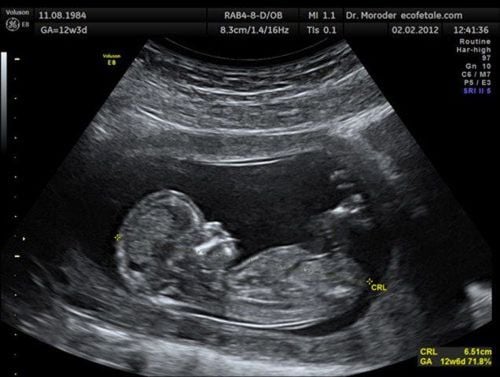

Siêu âm dây rốn, siêu âm bánh nhau là những siêu âm phần phụ của thai đóng vai trò quan trọng giúp phát hiện những bất thường ảnh hưởng đến thai nhi.

Hình ảnh siêu âm bánh nhau bình thường cho thấy những đặc điểm bình thường về cấu trúc, các chỉ số sinh trắc, vị trí bám của bánh nhau.

• Cấu trúc bánh nhau bình thường có hình bán nguyệt, vị trí kế cận với thành tử cung và có thể được xác định rõ từ tuần thứ 11.

• Siêu âm bánh nhau cho thấy cấu trúc bánh nhau bình thường gồm 3 phần riêng biệt là màng đáy, màng đệm và mô nhau thai. Cấu trúc nhau thai phát triển trong suốt thai kỳ.